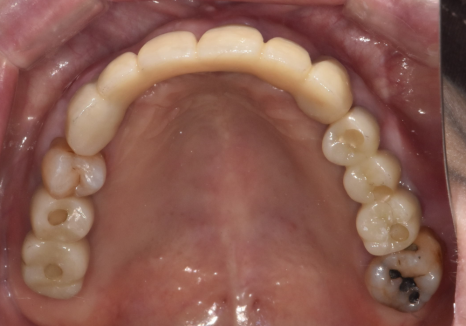

다행히 뼈이식 부위도 잘 자리를 잡았고

임플란트도 아주 튼튼하게 고정된 것을 확인 후

보철을 올려드렸습니다.

이제는 뿌리만 남았던 치아들 대신

튼튼한 치아로 편안하게

식사하실 수 있게 되었습니다.^^